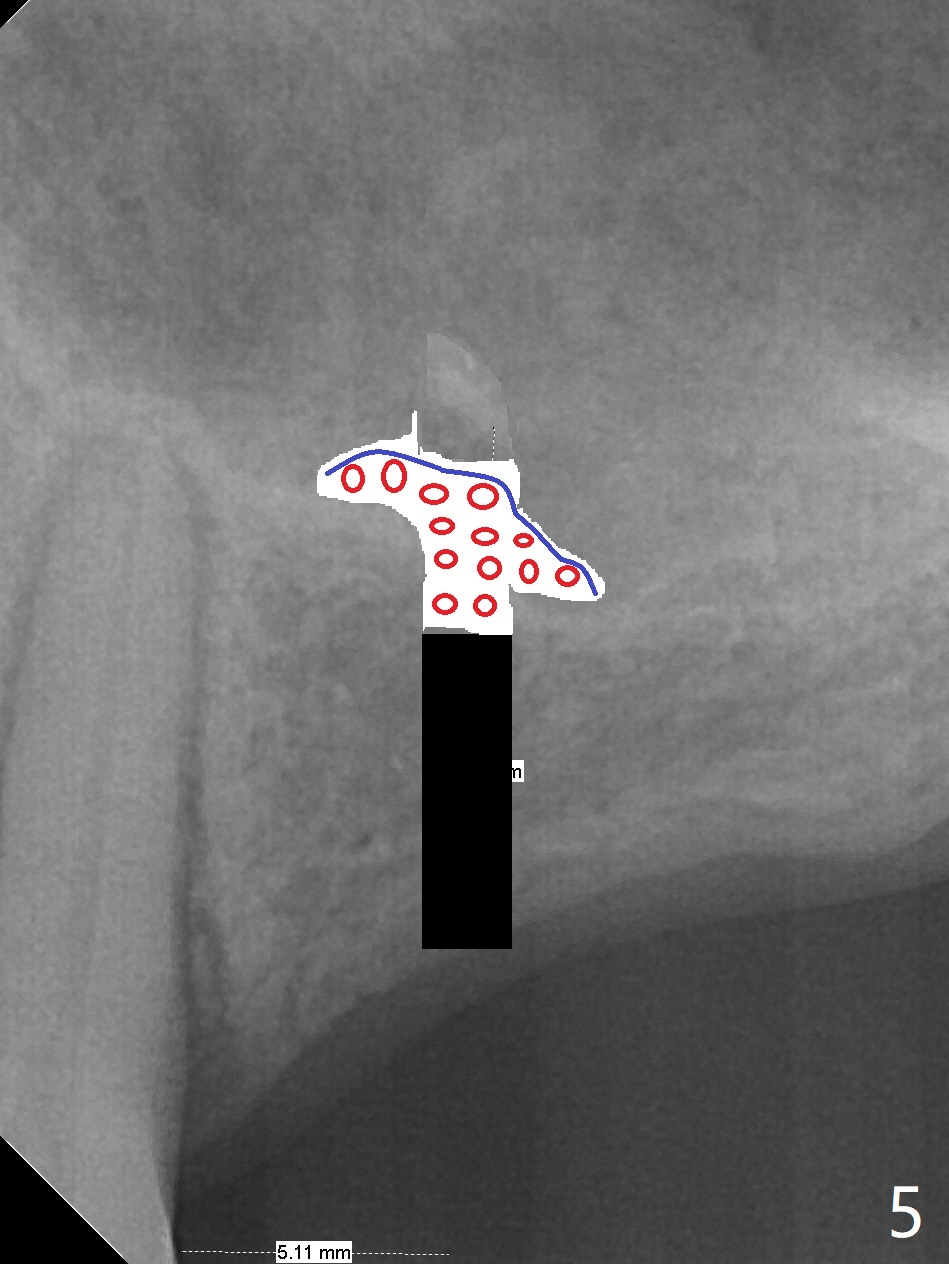

A 57-year-old woman has lost #14,15 and 18 for a while (Fig.1). Because of fear, an implant will be placed at #14 first (Fig.2). After use of Magic Drill for 5 mm (Fig.3), Magic Lifter will be used for lift (Fig.4). Following placement of PRF membrane (Fig.5 blue) and Vanilla Graft (red circles), a dummy implant is placed for additional lift (Fig.6 green). With placement of a larger and probably longer definitive implant, the graft may migrate distal due to gravity in sleep (Fig.7 arrow). In a few months, the bone height at #15 may increase to facilitate implant placement at #15.